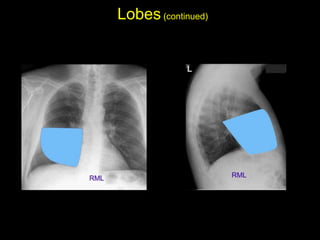

The document discusses the anatomy of the chest x-ray and CT scan by describing the lobes of the lungs and their locations. It also mentions the heart, mediastinum, hilum, and ribs. Several axial, coronal, and sagittal CT images are included with labels pointing out structures like the trachea, bronchi, lobes of the lungs, and fissures. In summary, the document provides an overview of lung and chest anatomy as seen on x-rays and CT scans through text descriptions and labeled medical images.